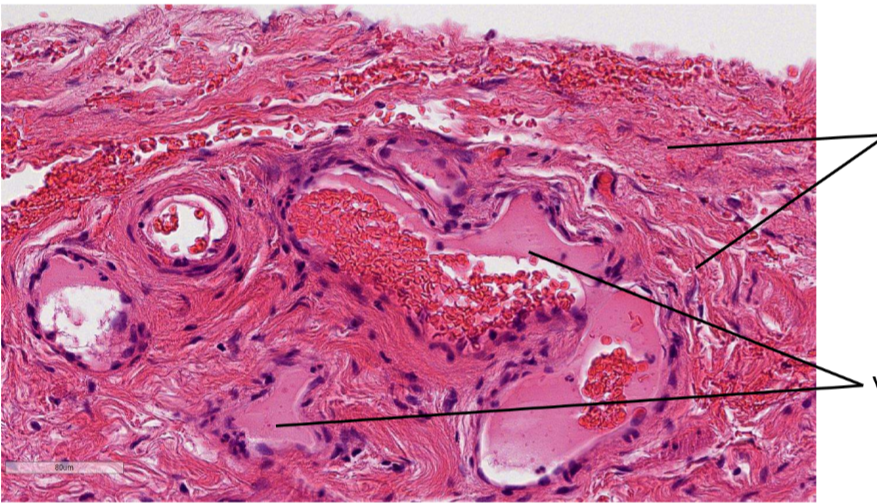

Lame de l’uretère au HE, au niveau de l’adventice

on le sait parce que fleche du haut= collagène (HE donc pas orange)

fleche en bas= VS